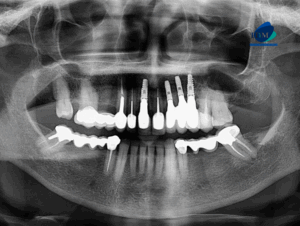

Paciente masculino de 67 años de edad, es referido al Instituto de Diagnóstico Maxilofacial – IDM para control tomográfico.En la radiografía panorámica (Figura 1), se

Paciente femenina de 61 años de edad acude al Instituto de Diagnóstico Maxilofacial – IDM (surco) para evaluación imagenológica por motivos protésicos.En la radiografía panorámica